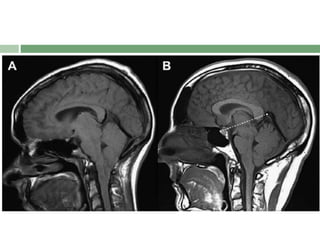

Acronym : SEEPS for MRI Features

 SEEPS

 S- Subdural fluid collections

 E- Enhancement of the pachymeninges

 E- Engorgement of the venous structures

 P- Pituitary enlargement

 S- Sagging of the posterior structures

Acronym : SEEPSfor MRI Features  SEEPS  S- Subdural fluid collections  E- Enhancement of the pachymeninges  E- Engorgement of the venous structures  P- Pituitary enlargement  S- Sagging of the posterior structures